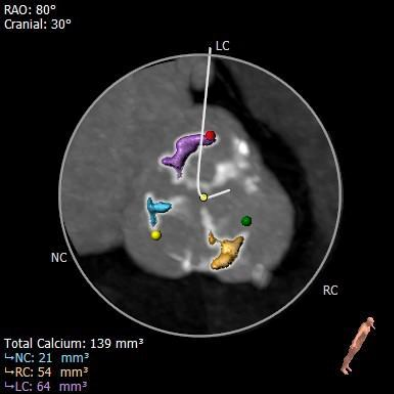

主动脉瓣瓣环周长69.8mm,平均周长径22.2mm。SOV:32.3mm*32.7mm*31.6mm,CT数据显示该患者为三叶式主动脉瓣,中度钙化,瓣叶增厚,钙化分布较均匀,主要分布于瓣叶边缘和管壁附着缘,瓣叶未见明显融合。

钙化分布: